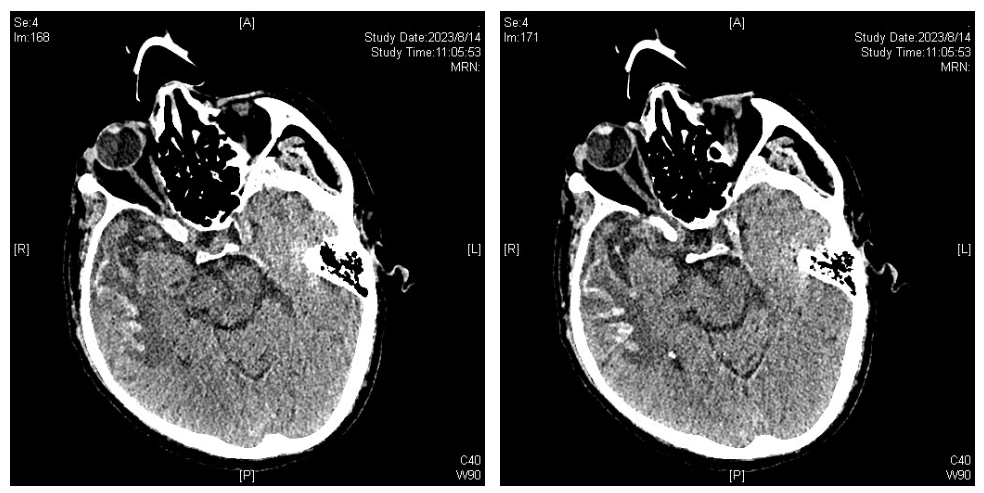

8月14日,复查影像学检查(依拉环素治疗14天),胸部CT:双肺感染较前吸收好转,双侧胸腔积液较前减少;头颅CT:右侧大脑半球低密度影范围较前增大,考虑脑梗塞并右侧颞叶出血可能,上颌窦炎,真菌感染可能。

图15. 胸部CT(2023-08-14)

图16. 头颅CT(2023-08-14)